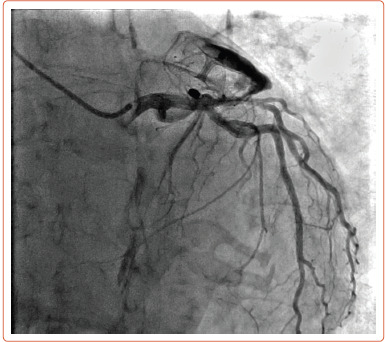

An 80-year-old patient presented with a rare complication: a late coronary-cameral fistula following implantation of an Amulet (Abbott) left atrial appendage occlusion device. Microperforations from the device's anchoring tines have previously been suggested as a possible mechanism of fistula formation, a complication reported in two other cases. We propose an alternative theory of potential collateralisation of the threatened appendage from the nearby circumflex artery.